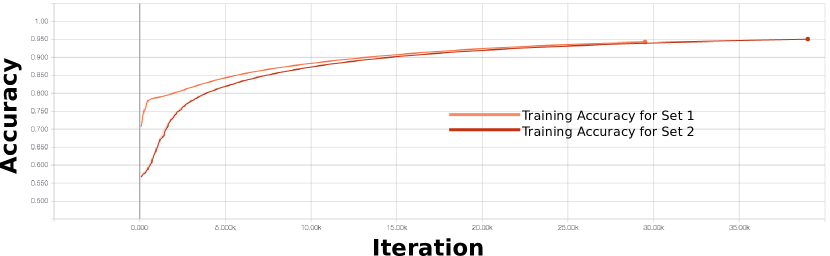

We empirically derived the parameters using a two-fold cross-validation approach on the training data (see Section II-A). Table I lists the parameters used for our training. Further information on our parameter validation is provided in Section SI of the Supplementary Materials.